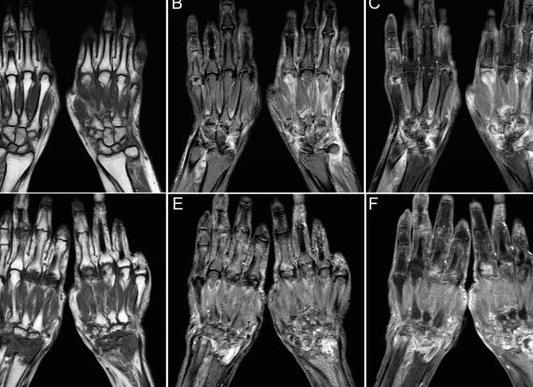

МРТ руки  – исследование для получения снимков верхней и нижней частей, в том числе локтей, рук, пальцев, мышц, других тканей. МРТ основывается на сканировании тканей радиоволнами. При проведении данного обследования не  используется ионизирующие облучение, оно не причинит вреда вашему здоровью. Так как можно получить изображения послойно, то это дает наиболее четкие изображения нужной части. Трехмерное изображение разрешает изучить любые самые небольшие изменения и аномалии. За одно обследование можно получить десятки, а иногда и сотни изображений в  различных плоскостях. Этот показатель  имеет большое значение, если необходимо исследовать опухоли, изменения при травмах, и также при обследовании перед операциями.

МРТ кисти рук дает возможность наиболее точно визуализировать травмированную или воспаленную область. В связи с тем, что на изображениях здоровые и больные клетки разного окраса, можно понять доброкачественность или злокачественность имеющихся новообразований.

МРТ кисти руки — это один из информативных методов оценки здоровья костей и мягких тканей верхних конечностей. Посредством этой процедуры можно диагностировать различные нарушения, начиная травмами и заканчивая онкологией. По качеству результатов МРТ уступает только артроскопии. Но этот метод исследования подразумевает нарушение целостности кожи. Без вмешательства нельзя ввести инструменты для медицинских манипуляций. Среди неинвазивных вариантов исследования МРТ на сегодняшний день нет равных.

Основное отличие компьютерной томографии от магнитно-резонансной состоит в большей степени информативности. С другой стороны, результаты обследования редко имеют значимые различия. Большая часть пациентов отдает предпочтение МРТ, поскольку такое исследование позволяет оценить состояние мягких тканей кисти. Благодаря этому методу специалист может визуализировать все структуры изучаемой области.

Информативность результатов МРТ ничем не уступает КТ, но для сканирования костных структур рекомендуется проводить диагностику с рентгенологическим излучением. Магнитно-резонансная томография дает более полную информацию о состоянии мягких тканей.